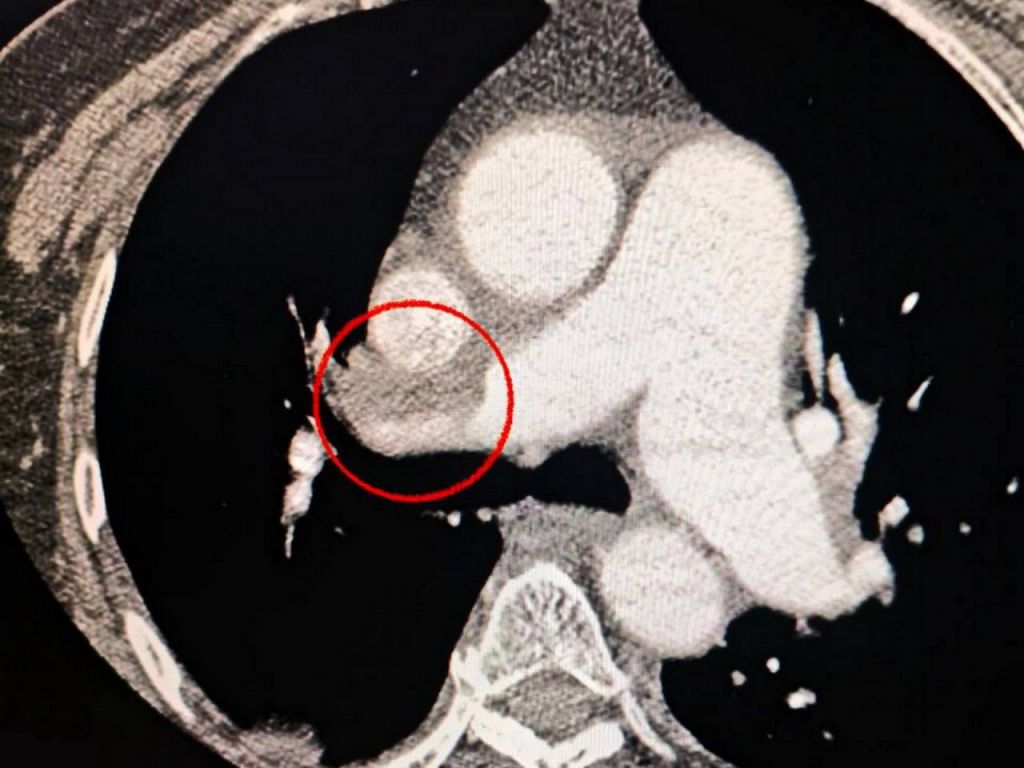

Пацієнтка потрапила до лікарні з ознаками важкого інсульту. Комп’ютерна томографія підтвердила закупорку середньої мозкової артерії. Однак лікарі помітили, що жінці важко дихати. Додаткове обстеження виявило ще одну смертельну небезпеку — тромбоемболію легеневої артерії. Мультидисциплінарна команда лікарів пішла на ризик і прийняла життєво необхідне рішення: провести тромбектомію (видалення тромбів) одночасно на двох критичних ділянках — у мозку та легенях.